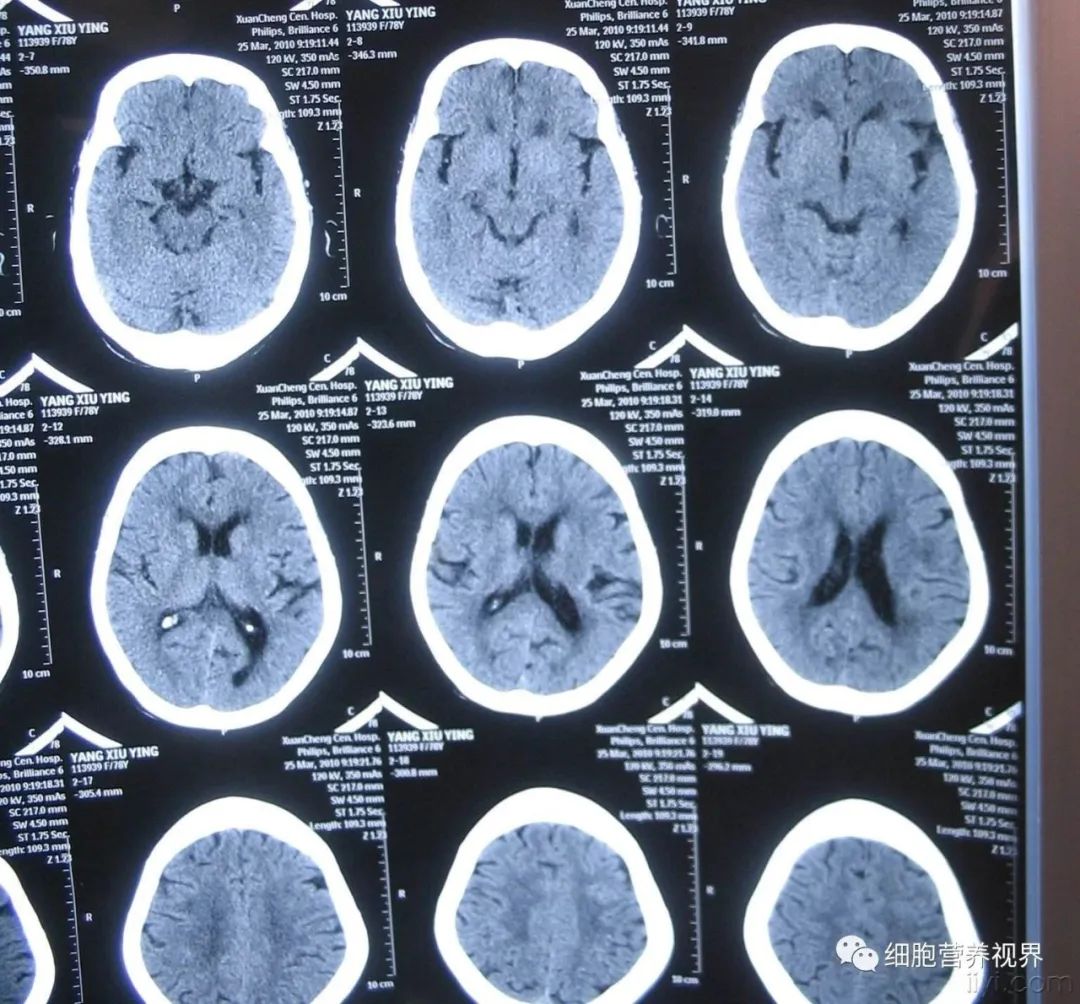

所谓脑梗,是脑卒中的一种,是大脑血管变细,或血栓堵塞导致血流凝滞的疾病。据有关统计显示,我国现有脑卒中患者7000万人,每年新发脑卒中200万人,每年脑卒中死亡人数为165万人,每21秒就有一个中国人死于脑卒中。

第一种是“动脉粥样硬化血栓性脑梗塞”,脑内大血管发生强动脉硬化是主要原因。血压升高,血管为了承受住压力,管壁会变厚变硬。这就是动脉硬化。血管壁变厚了,血管内就会变窄。再在变厚的血管壁上加上过多的胆固醇等(这叫做动脉粥样硬化),血管就会变得更窄,血栓堵塞,血液凝滞。

第二种是“腔隙性脑梗塞”,腔隙性脑梗塞是脑梗塞的一种特殊类型,是在高血压、动脉?;幕∩?,脑深部的微小动脉发生闭塞,引起脑组织缺血性软化病变。其病变范围一般为2-20毫米,其中以2-4毫米者最为多见。但是由于堵塞的血管太细,血管会被挤破,所以也可以叫自爆型。虽然是小梗塞大多症状较轻,但有容易复发、脑内多处并发的情况,所以也需引起注意。

第三种是“心源性脑梗塞”,这一类别是指心脏里面的栓子脱落,堵塞颅内外动脉。心房纤颤、二尖瓣机械瓣膜是主要诱因。心房颤动是心律不齐的一种,心脏不仅起着将血液送至全身的泵的作用,由于其节奏变得不稳定,导致血液在心脏中停滞,形成血栓。这个血栓的一部分剥落通过血管,在大脑堵塞,这是心源性脑栓塞症。